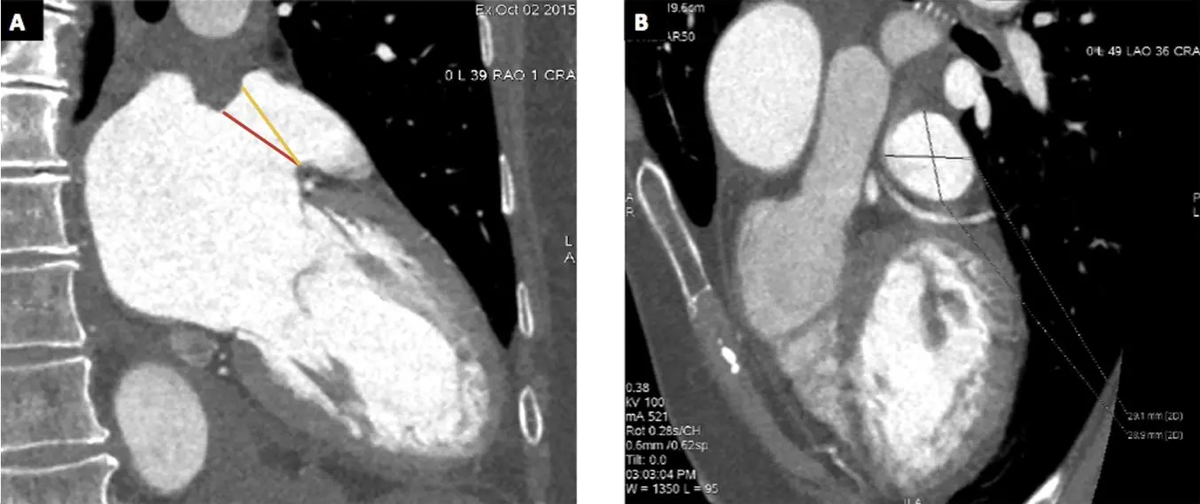

«Мы стремились оценить дополнительную ценность 3D-печати ушка левого предсердия (УЛП), полученного на основе компьютерной томографии сердца (КТС), в определении размера устройств для окклюзии УЛП (LAAO) по сравнению со стандартными измерениями, используя в качестве конечной точки возникновение протечки (недостаточного закрытия) УЛП». Методы и материалы

В этом пилотном ретроспективном исследовании случай-контроль «мы оценили 6 пациентов с протечкой УЛП (случаи) и 14 подобранных пациентов без протечки УЛП (контроль) после LAAO. Все пациенты перед процедурой LAAO прошли КТС и чреспищеводную эхокардиографию (ЧПЭ). Процедура LAAO выполнялась под контролем ЧПЭ и кардиоангиографии (КА), а размер устройства определялся на основе ЧПЭ, КТС и КА. Для каждой группы была изготовлена персонализированная 3D-модель УЛП с использованием предоперационных КТ-изображений. Модель

«Мы стремились оценить дополнительную ценность 3D-печати ушка левого предсердия (УЛП), полученного на основе компьютерной томографии сердца (КТС), в определении размера устройств для окклюзии УЛП (LAAO) по сравнению со стандартными измерениями, используя в качестве конечной точки возникновение протечки (недостаточного закрытия) УЛП».

В этом пилотном ретроспективном исследовании случай-контроль «мы оценили 6 пациентов с протечкой УЛП (случаи) и 14 подобранных пациентов без протечки УЛП (контроль) после LAAO. Все пациенты перед процедурой LAAO прошли КТС и чреспищеводную эхокардиографию (ЧПЭ). Процедура LAAO выполнялась под контролем ЧПЭ и кардиоангиографии (КА), а размер устройства определялся на основе ЧПЭ, КТС и КА. Для каждой группы была изготовлена персонализированная 3D-модель УЛП с использованием предоперационных КТ-изображений. Модель была в конечном итоге напечатана на настольном 3D-принтере Form 2* (Formlabs Inc., MA, USA), основанном на технологии стереолитографии. Зона фиксации (landing zone) УЛП затем была измерена вручную с помощью цифрового штангенциркуля. Для подтверждения выбора использовали визуальную проверку позиционирования окклюдера УЛП. Наконец, размер, рекомендованный 3D-печатной моделью, сравнивался с размером имплантированного устройства для оценки соответствия, занижения или завышения размера и его связи с послеоперационной протечкой».

«Сравнение размера имплантированного протеза с размером, определенным с помощью 3D-печатной модели, показало занижение размера у 11 пациентов (55%), соответствие у 7 пациентов (35%) и завышение в 2 случаях (10%)... Распространенность протечки УЛП была значительно выше в подгруппе пациентов с занижением размера имплантированного протеза (6 из 11 пациентов против 0 из 9 пациентов, p = 0,019)».

«Используя протечку УЛП в качестве первичной конечной точки, 3D-печатные модели УЛП, полученные на основе КТС, по-видимому, более точны для подбора размера устройства LAAO по сравнению со стандартной оценкой, основанной на предоперационных ЧПЭ, КТС и КА, независимо от имплантированного устройства».

«3D-печать УЛП, полученного на основе КТС, осуществима и может добавить ценности к определению размера протеза устройства LAAO, полученному на основе КТС, ЧПЭ или КА, за счет снижения протечки УЛП».